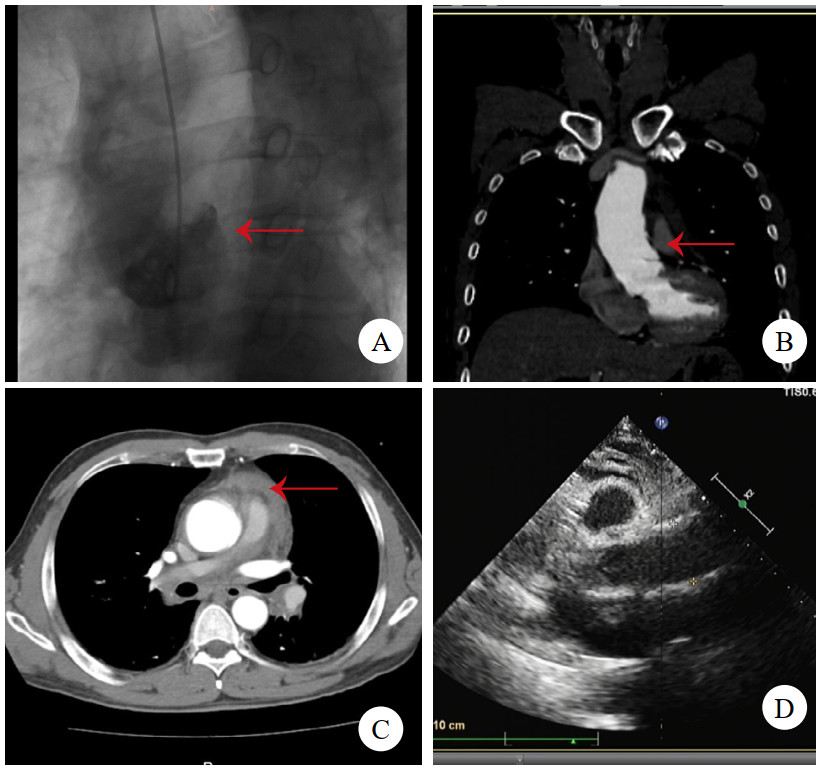

病例2,男,47岁,因“突发背痛伴胸闷1 h”入院。查心电图提示下壁导联ST段抬高0.1 mv,TTE提示节段性室壁运动异常,升主动脉及窦内径增宽,肌钙蛋白阴性,考虑“急性心肌梗死”。行急诊冠脉造影术,见冠状动脉通畅,加行主动脉造影见根部后壁斜行龛影(图 2A)。予查主动脉CTA,见主动脉根部左冠状动脉开口上方条状影(图 2B),该处主动脉直径为44 mm,升主动脉周围少量心包积血(图 2C),提示LIT。建议急诊开胸手术,患方自行至外院行升主动脉置换术,术中所见符合LIT,术后2个月至本院复查TTE,见升主动脉人工血管通畅(图 2D),无室壁运动异常。后门诊随访5年,情况平稳。

| 注:A为主动脉造影,箭头示根部后壁斜行龛影;B为主动脉CTA,箭头示左冠状动脉开口上方条状影;C为箭头示升主动脉周围少量心包积血;D为TTE见升主动脉人工血管通畅 图 2 例2患者主动脉根部造影、术前CT及术后TTE影像 |